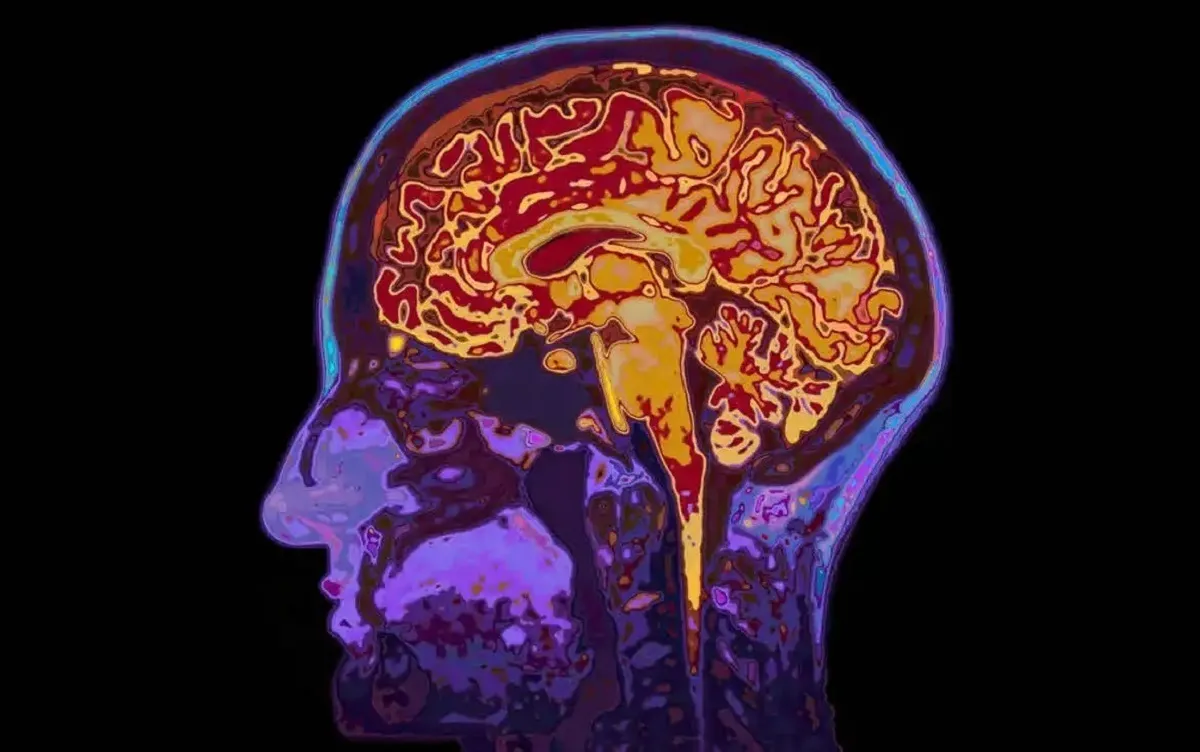

به گزارش ایسنا، یک مطالعه تازه در سوئد نشان میدهد افرادی که خواب بیکیفیتی دارند، مغزشان در اسکنها پیرتر از سن واقعیشان به نظر میرسد.

به گزارش نیوزمدیکال، این مطالعه با مشارکت ۲۷ هزار و ۵۰۰ فرد میانسال و سالمند انجام شد که همه آنها امآرای مغز انجام دادند و متخصصان با کمک یادگیری ماشینی بر اساس بیش از ۱۰۰۰ شاخص امآرای، سن زیستی مغز آنها را تخمین زدند.